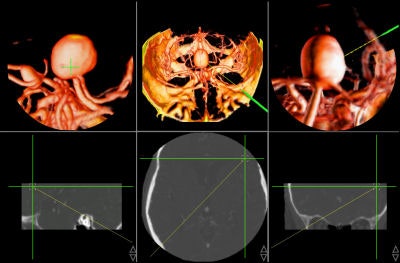

Postoperative validation

Once the surgery is over, 3D imaging can aid the physician in assessing the success of the procedure. In thoracic aorta studies, volumetric reconstruction provides detailed exploration of the interior of the aorta and its major branches.

Figure 8, below, illustrates one case in which a thoracic aortic aneurysm was repaired with an endoluminal stent graft. The chosen color and opacity scale results in the clear delineation of the stent-graft supports from the aortic wall. This demonstrates the adequacy of the stent-graft placement and highlights the regions where the metallic struts of the stent graft project into the aortic lumen. In patients with subsequent single or bilateral lung transplantation, volumetric reconstruction of postoperative data can illustrate all bronchial structures and assess endobronchial stent placement.

![]() |

| Figure 8 |